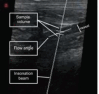

Ultrasound (USG) is a valuable diagnostic tool for evaluating the gastrointestinal tract of cats, providing noninvasive and dynamic information. B-mode USG allows evaluation of intestinal wall thickness, stratification, motility, and adjacent structures, such as lymph nodes and peritoneum. The stomach and intestinal segments can be differentiated based on their location, wall stratification, and relationships with surrounding organs. Normal ultrasound parameters, including gastric and intestinal wall thickness, peristaltic activity, and luminal content appearance, have been established for cats. Doppler ultrasound was used to assess vascular flow in the celiac and cranial mesenteric arteries and detect hemodynamic changes associated with gastrointestinal diseases. Alterations in flow velocity, resistivity index, and pulsatility index provide insights into vascular resistance and parenchymal function. Doppler velocimetry can also differentiate normal from pathological flow patterns, thereby aiding in the diagnosis of inflammatory, neoplastic, and ischemic conditions. Ultrasound findings of feline chronic enteropathy include wall thickening, loss of layering, and altered vascular supply. Lymphoplasmacytic enteritis and alimentary lymphoma, which are common in cats, present overlapping USG features, requiring histopathology for definitive diagnosis. Doppler alterations in the mesenteric arteries reflect gastrointestinal inflammation and ischemia, highlighting their potential as complementary diagnostic tools. Although B-mode and Doppler ultrasound are effective in identifying gastrointestinal abnormalities, further studies are needed to establish reference values and refine their clinical applications. The integration of these techniques enhances the noninvasive assessment of feline enteropathies and contributes to improved diagnosis and management. This review explores the use of B-mode and Doppler ultrasound for assessing the stomach and intestines in healthy and diseased felines.